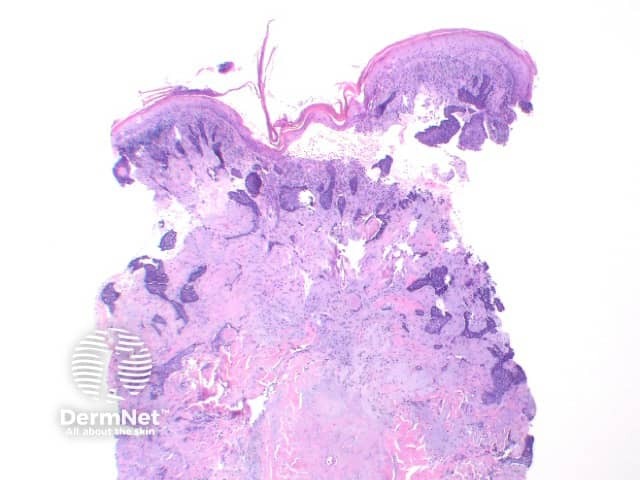

The key feature of basal cell carcinoma at low power magnification is of a basaloid epithelial tumour arising from the epidermis (figure 1). The basaloid epithelium typically forms a palisade with a cleft forming from the adjacent tumour stroma (figure 2). Centrally the nuclei become crowded with scattered mitotic figures and necrotic bodies evident (figure 3). A useful distinguishing feature from other basaloid cutaneous tumours is the presence of a mucinous stroma (figure 4). Some tumours may also show foci of regression, seen as areas of eosinophilic stroma with lack of basaloid nests.

Figure 2

Superficial BCC: This variant show multifocal nests of atypical basaloid epithelium arising as buds from the basal layer of the epidermis. These nests remain confined to the papillary dermis (Figure 5)